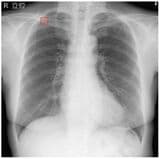

医師の診断補助や早期発見に活用が進むAI医療機器。画像解析や心電図解析、胃がん診断支援など次世代の医療を支える現場事例が登場しています。しかし普及の壁には、厳格な承認審査や保険適用の遅れといった課題も。日本の医療とAIはどこまで進化できるのでしょうか。(このリード文はAIが作成しました)